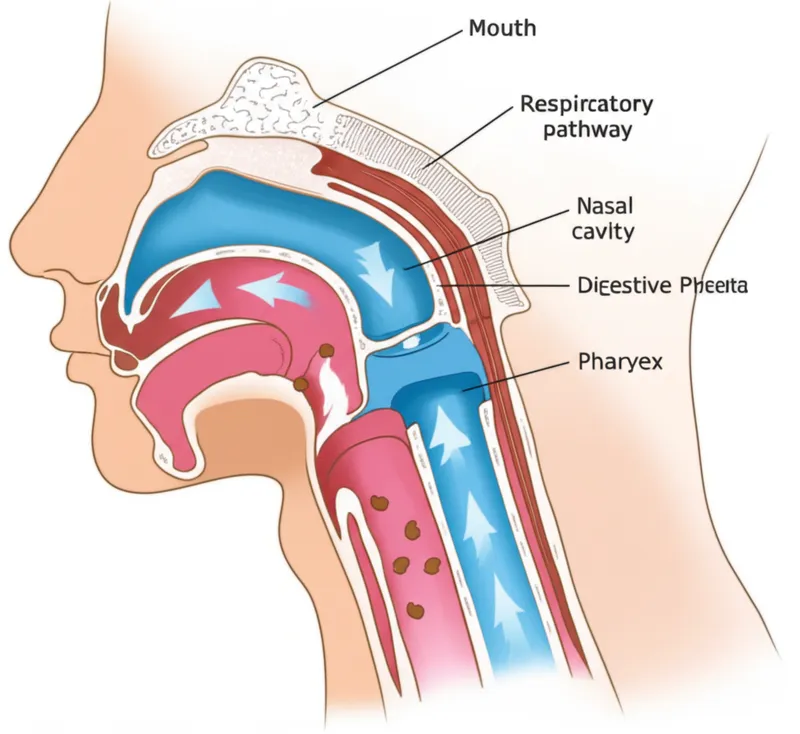

sore throat

inflammationnoun